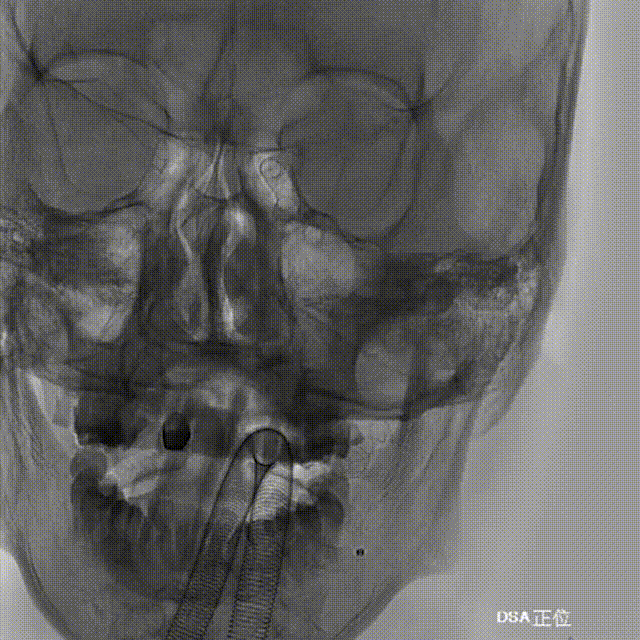

Tubridge Plus Case 1